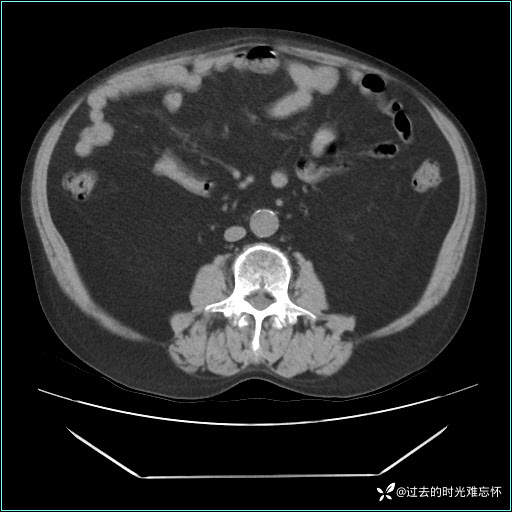

患者男,71 岁,因「反复腹痛腹胀 1 月」入院。

现病史:患者 1 月前无明显诱因下出现腹痛腹胀症状,腹痛呈隐痛,当时未予以重视,后症状有所加重,常在进食辛辣刺激油腻等食物后出现腹痛,口服药物治疗症状能得到控制,病情控制一般。现为求诊治来我院,拟“腹痛”入院。病程中患者神志清楚,精神一般,无咳嗽咳痰,无恶心呕吐,近期体重无明显变化。